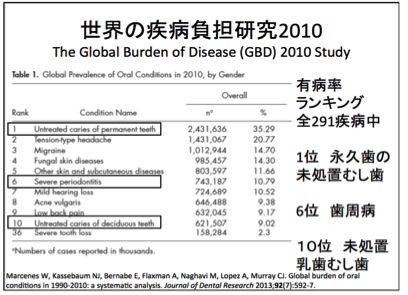

また、世界的にも、虫歯や歯周病といったお口の病気は疾病負担がトップクラスだと報告されています。つまり、誰もがかかりやすい病気であるということです。